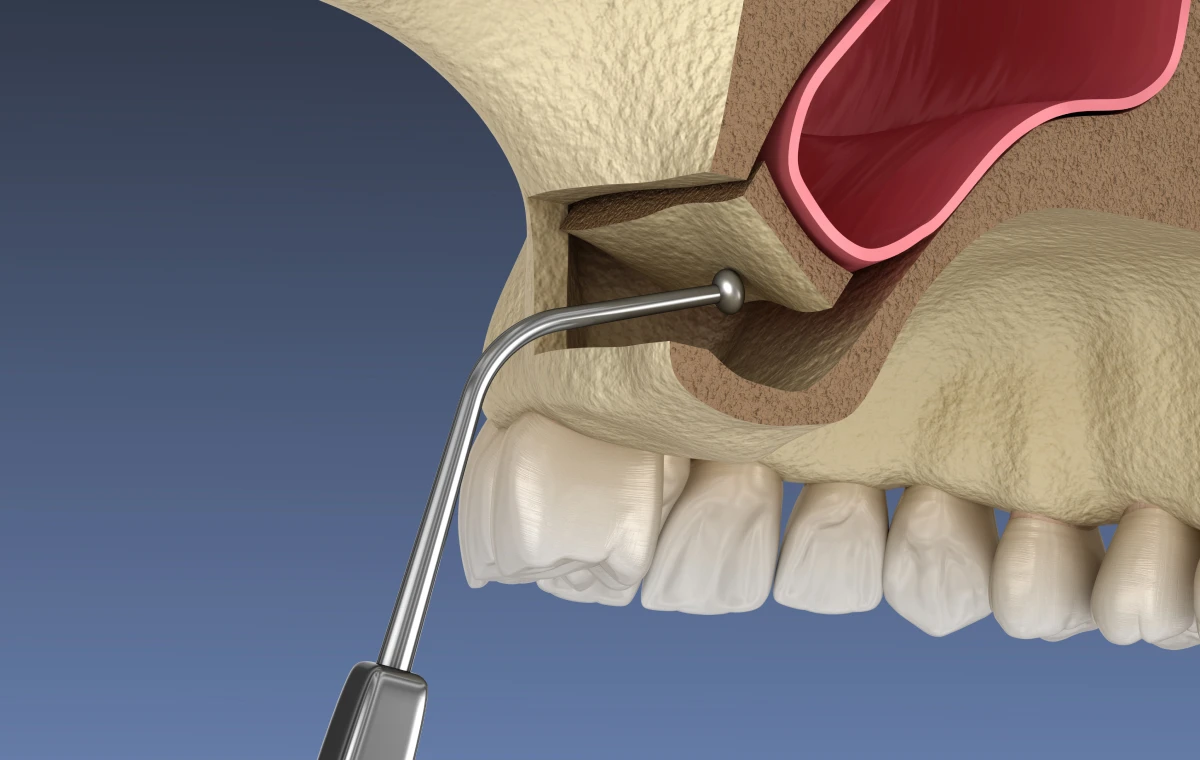

La voie latérale

C’est la méthode la plus répandue. Le praticien crée une fenêtre sur la paroi externe du maxillaire, soulève la membrane et insère le matériau osseux.

- Indiquée pour des pertes osseuses importantes.

- Permet un gain osseux significatif (jusqu’à 10 mm).

- Cicatrisation plus longue mais prévisible.

Cette approche mini-invasive utilise le site de forage implantaire pour accéder au sinus. La membrane est délicatement soulevée par des ostéotomes ou des instruments spécifiques.

Pendant l’intervention

L’acte chirurgical se déroule sous anesthésie locale, éventuellement complétée par une sédation pour plus de confort. Le praticien réalise une incision gingivale afin d’accéder à la zone à traiter, puis procède au soulèvement contrôlé de la membrane sinusienne. Le matériau de greffe osseuse est ensuite mis en place pour favoriser la régénération, avant que la zone ne soit refermée à l’aide de sutures résorbables.